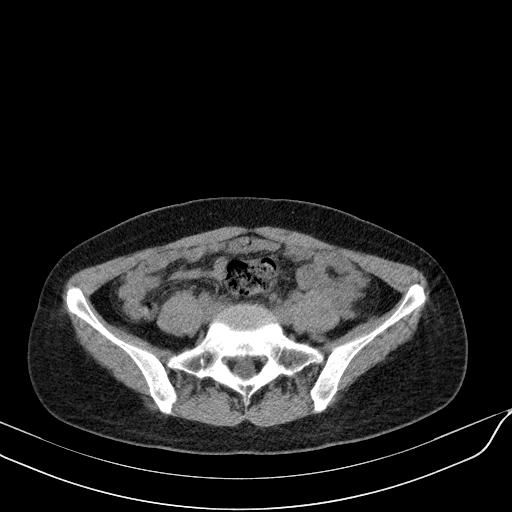

标题: CT23965:无外伤史,下腹痛 [打印本页]

标题: CT23965:无外伤史,下腹痛

肠道未准备,继续往下扫,乙状结肠占位不排除。建议钡灌或结肠镜检查。

乙状结肠占位不排除

未见明显异常改变,做个气钡双重造影除外一下结肠病变,无外伤史为啥不常规喝泛影葡胺水对比剂再扫ct呢?

扫描时应做肠道准备,口服稀释造影剂。

回肠间质瘤?

肠道肿瘤,建议行钡剂灌肠检查。